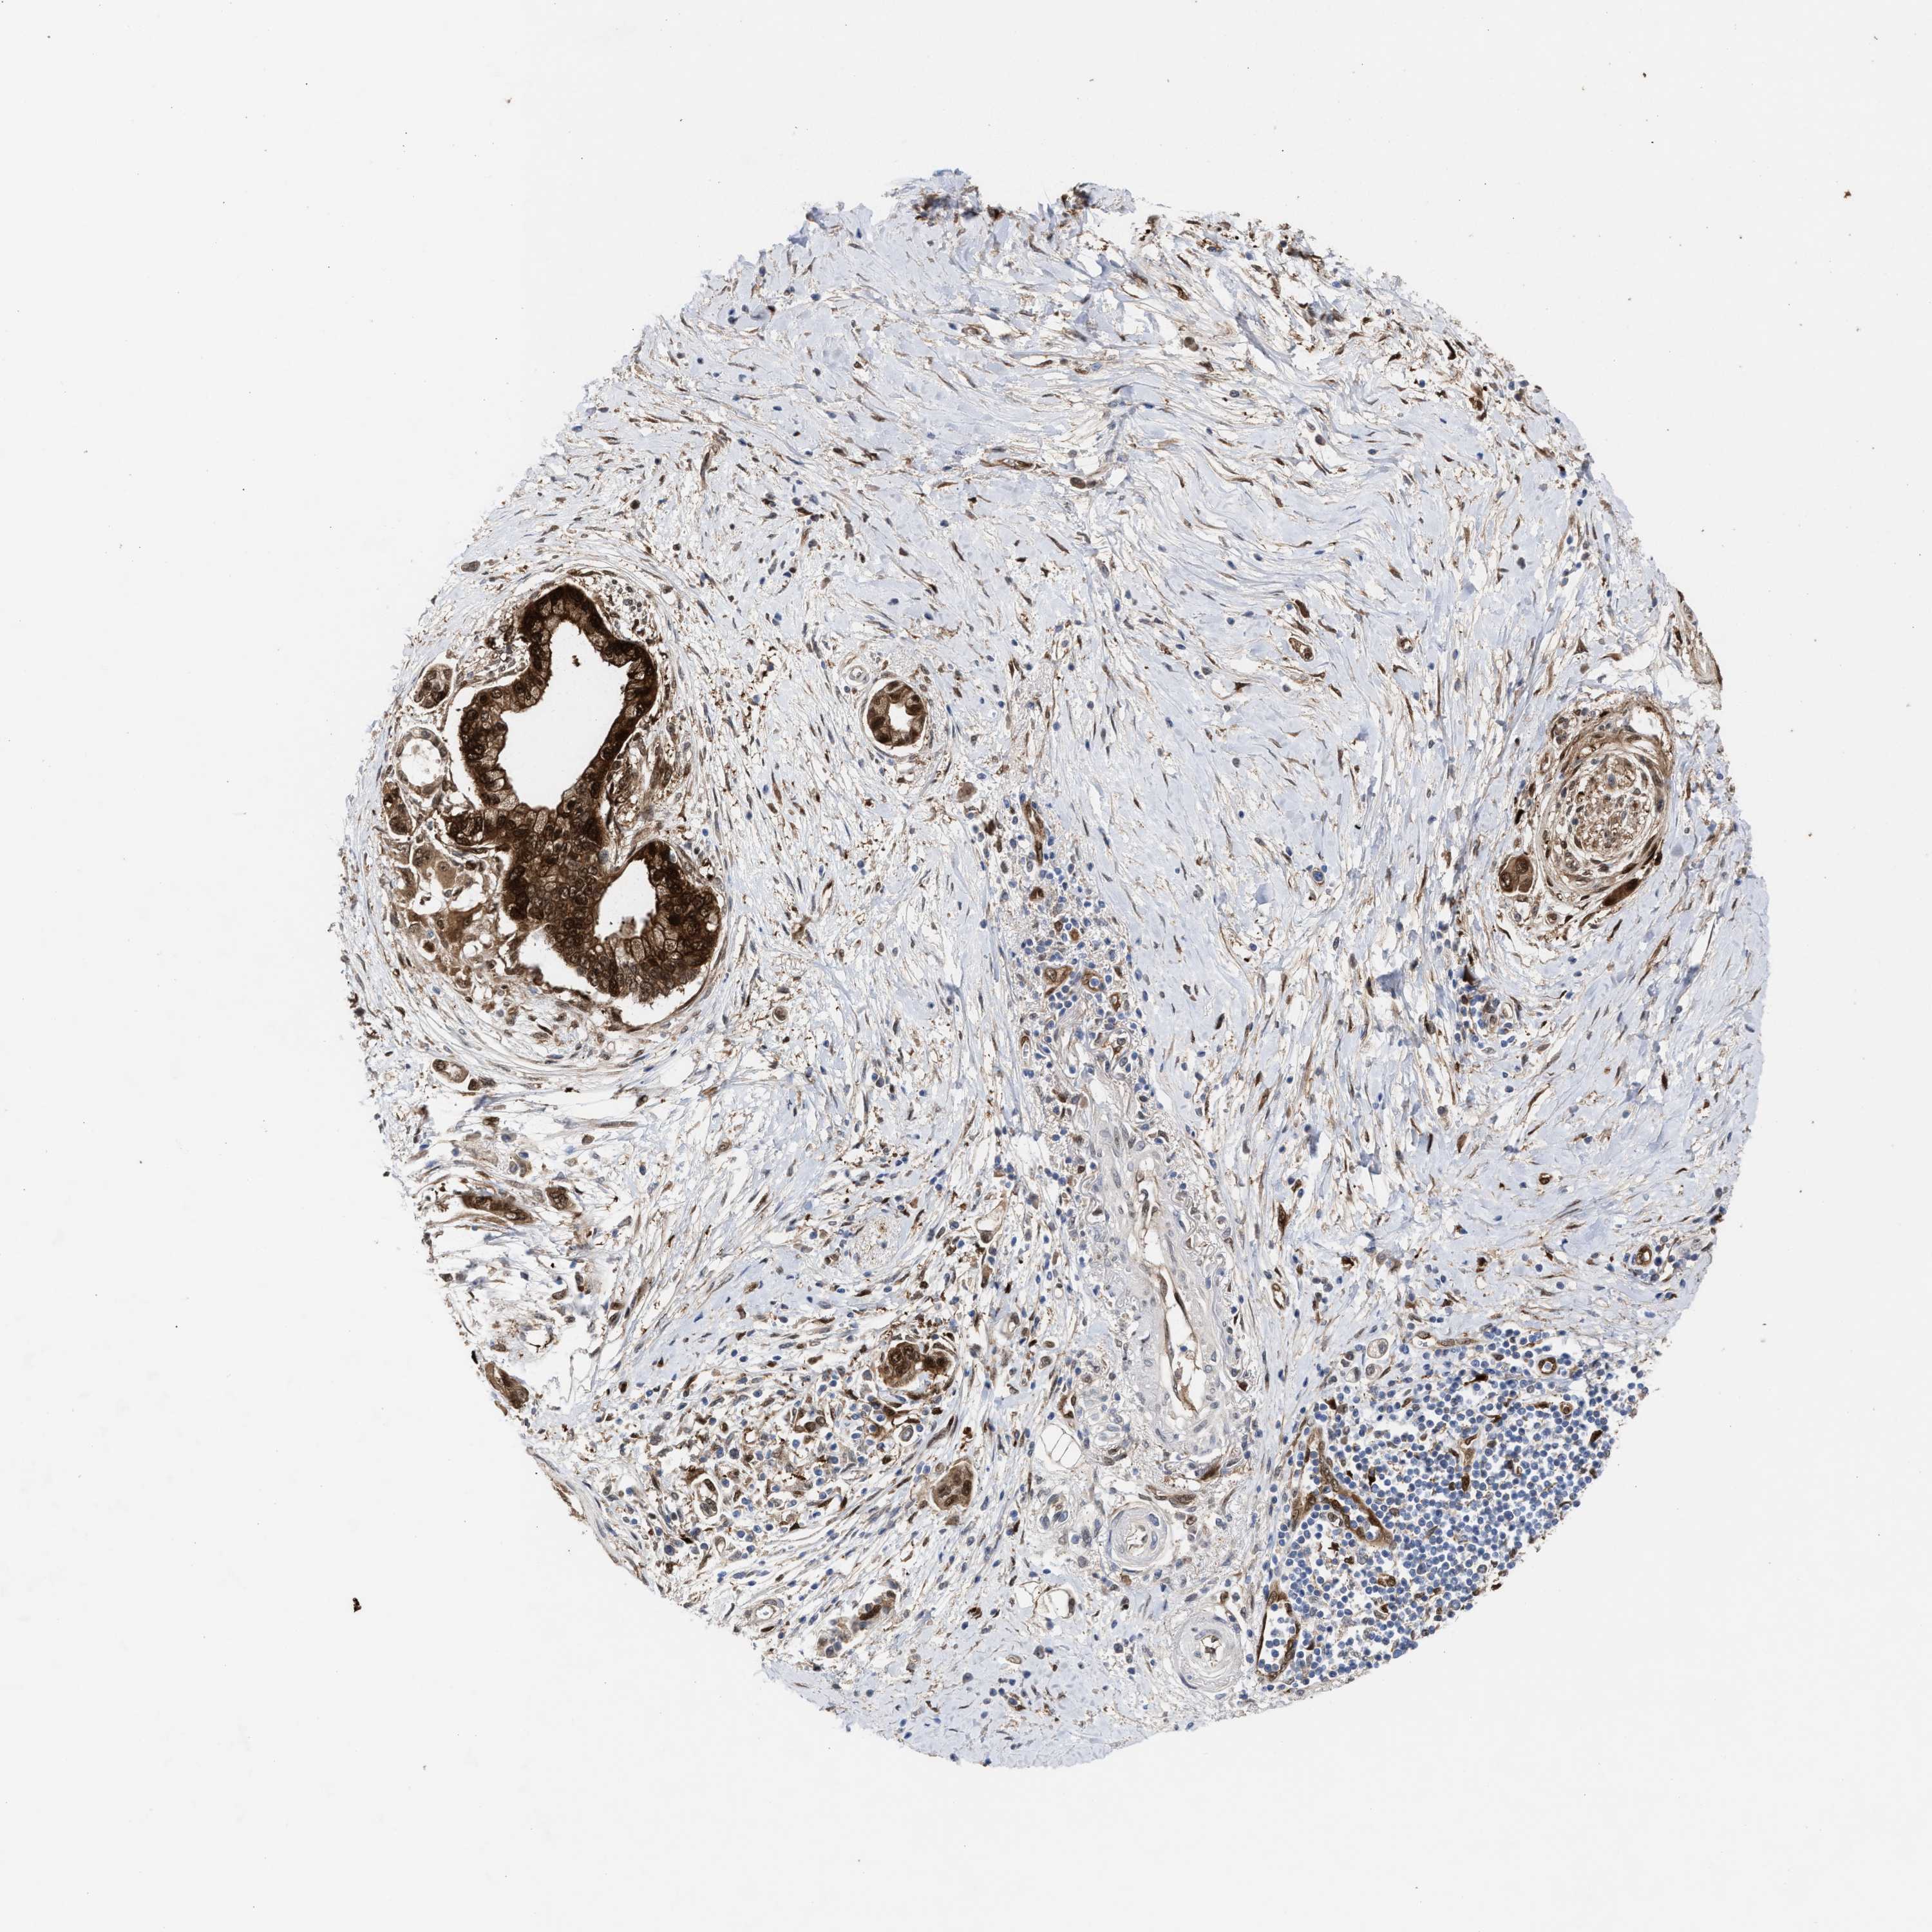

PANCREATIC CANCER - Protein expressioni

A mouse-over function shows sample information and annotation data. Click on an image to view it in a full screen mode. Samples can be filtered based on level of antibody staining by selecting one or several of the following categories: high, medium, low and not detected. The assay and annotation is described here.

Note that samples used for immunohistochemistry by the Human Protein Atlas do not correspond to samples in the TCGA dataset.

Antibody stainingi

Antibody staining in the annotated cell types in the current human tissue is reported as not detected, low, medium, or high, based on conventional immunohistochemistry profiling in selected tissues. This score is based on the combination of the staining intensity and fraction of stained cells.

Each image is clickable and will lead to virtual microscopy that enables deeper exploration of all samples and also displays staining intensity scores, fraction scores and subcellular localization as well as patient and tissue information for each sample.

Antibody HPA022012

Antibody HPA028742

Antibody CAB017479

Staining

High

Medium

Low

Not detected

Intensity

Strong

Moderate

Weak

Negative

Quantity

>75%

75%-25%

<25%

None

Location

Nuclear

Cytoplasmic/membranous

Cytoplasmic/membranous,nuclear

Adenocarcinoma, NOS

Adenocarcinoma, metastatic, NOS